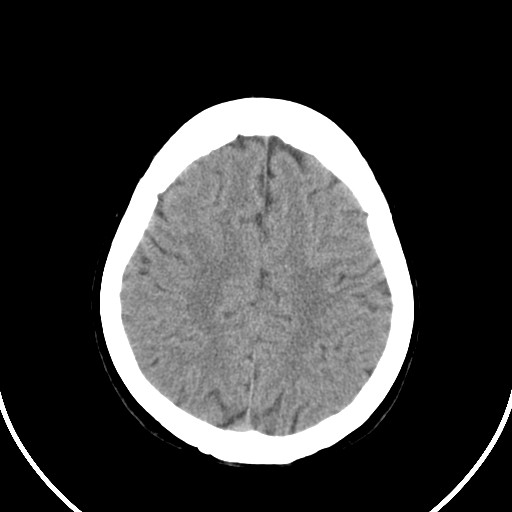

女,56岁,右中指淤肿,右手麻痹1天

右侧侧脑室旁脑白质腔隙性脑梗死。

右侧基底节多发小梗塞

作者: huangyinshan    时间: 2009-8-25 15:37

右基底结区腔梗

右侧基底节区腔隙性脑梗塞

右侧基底节多发腔梗!

双侧侧脑室额角旁对称性略低密度影,边缘模糊,无占位效应,考虑轻度脑白质稀疏症(病人有高血压吗).,右枕叶低密度影多为伪影,不放心薄扫一下.

考虑脑白质病。

考虑脑白质病

右枕叶条状低密度影不应该忽略可能极具意义